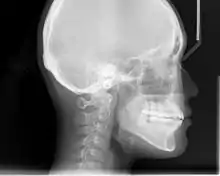

Cephalometric radiographs

Cephalometric analysis depends on cephalometric radiography to study relationships between bony and soft tissue landmarks and can be used to diagnose facial growth abnormalities prior to treatment, in the middle of treatment to evaluate progress, or at the conclusion of treatment to ascertain that the goals of treatment have been met.[5] A Cephalometric radiograph is a radiograph of the head taken in a Cephalometer (Cephalostat) that is a head-holding device introduced in 1931 by Holly Broadbent Sr. in USA.[6] The Cephalometer is used to obtain standardized and comparable craniofacial images on radiographic films.

Lateral cephalometric radiographs

Lateral cephalometric radiograph is a radiograph of the head taken with the x-ray beam perpendicular to the patient's sagittal plane. Natural head position is a standardized orientation of the head that is reproducible for each individual and is used as a means of standardization during analysis of dentofacial morphology both for photos and radiographs. The concept of natural head position was introduced by Coenraad Moorrees and M. R Kean in 1958[9][10] and now is a common method of head orientation for cephalometric radiography.[11][12]

Registration of the head in its natural position while obtaining a cephalogram has the advantage that an extracranial line (the true vertical or a line perpendicular to that) can be used as a reference line for cephalometric analysis, thus bypassing the difficulties imposed by the biologic variation of intracranial reference lines. True vertical is an external reference line, commonly provided by the image of a free-hanging metal chain on the cephalostat registering on the film or digital cassette during exposure. The true vertical line offers the advantage of no variation (since it is generated by gravity) and is used with radiographs obtained in natural head position.